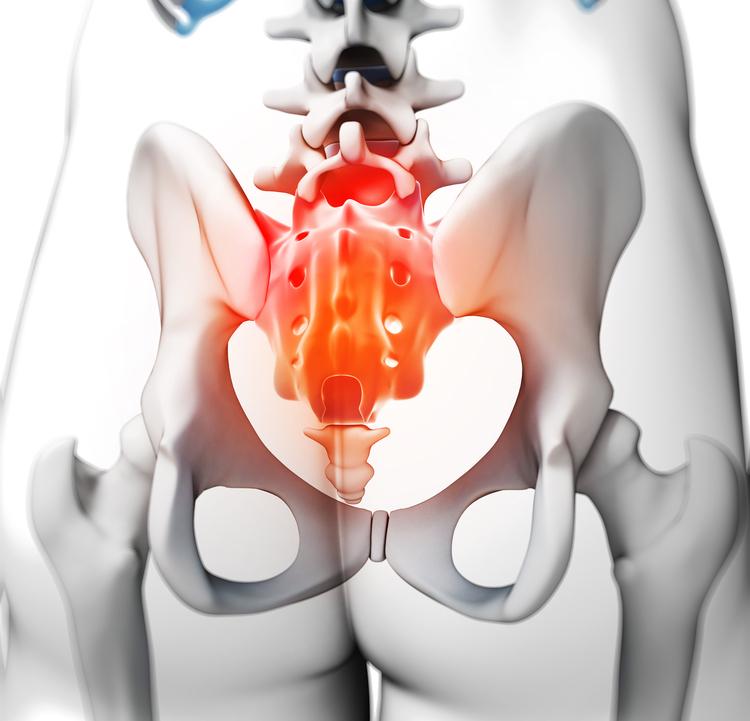

Coxidinia

La Coxidinia es un trastorno que afecta a la zona interior del coxis, es decir, a la estructura que comunica directamente con la columna vertebral en la zona más baja. Hay muchos factores que pueden derivar en este trastorno, cómo un trauma, una caída, o realizar siempre el mismo ejercicio (por ejemplo, montar en bicicleta repetidamente). También puede tener su origen en lesiones que se hayan producido en el momento del parto, o tras haberse fracturado ciertos huesos.

No obstante, también se podría presentar de forma espontánea sin que se haya producido ninguna de las condiciones citadas.

Los síntomas  de la Coxidinia afectan sobre todo a la sensibilidad: tanto la zona de los tendones, cómo la de los ligamentos, empezaran a ser más sensibles y esto provocará un incremento considerable del dolor.